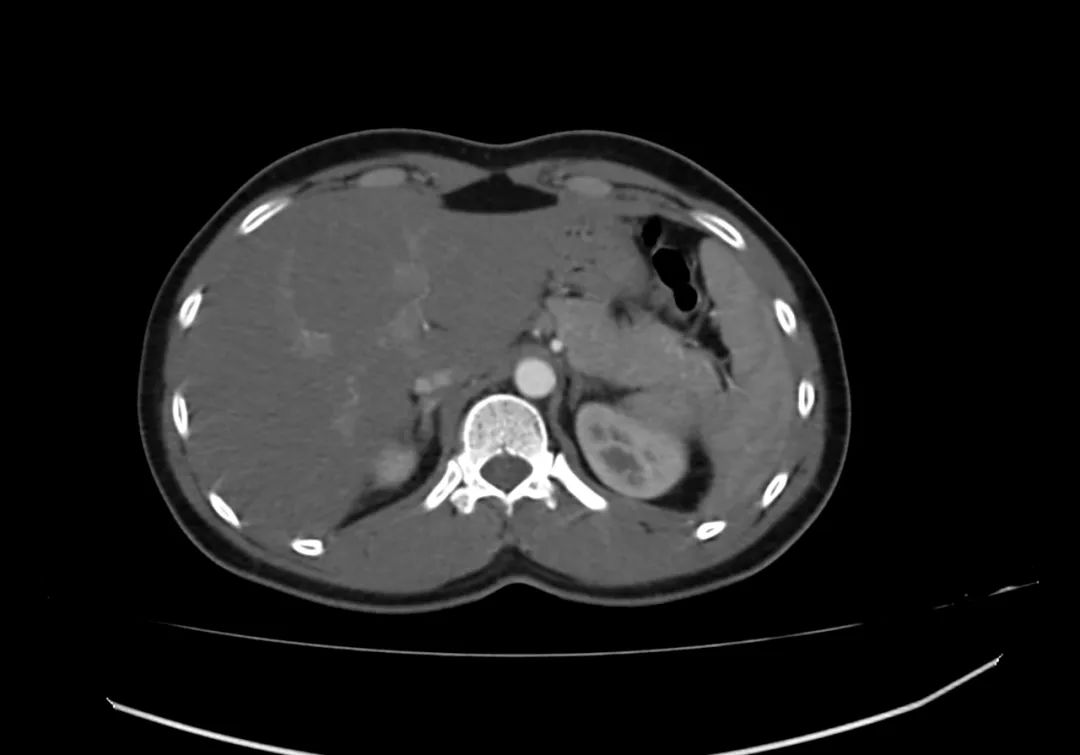

动脉期上腹部轴向增强图像显示胰腺完全包围十二指肠第二部,与完全性环状胰腺一致。

带注释的动脉期图像显示增强胰腺实质(标记为P)完全包裹十二指肠(标记为D)。

环状胰腺是由腹芽不旋转导致十二指肠被胰腺不同程度包裹的结果。完全性环状胰腺出现在新生儿有梗阻,并可偶然发现在成人,胰腺炎可能是成人的一种表现特征。